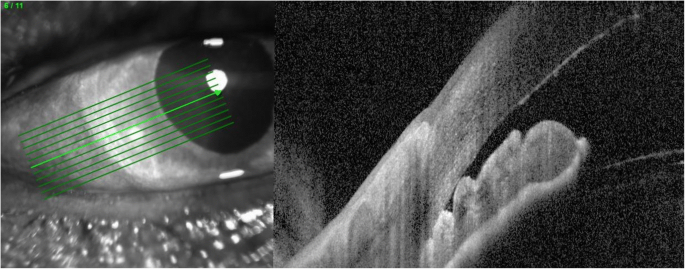

On examination the patient was found to have reduced VA in the right eye 6/12 with an injected conjunctiva, cloudy cornea and a mid-dilated pupil with a very shallow anterior chamber (AC) and closed irido-corneal angle on gonioscopy (Figs. 1 and 2). Fundus exam revealed a large supero-nasal suprachoroidal haemorrhage not involving the macula. His right intra-ocular pressure (IOP) was 42 mmHg. The left eye had a VA of 6/6 with a deep AC and IOP of 12 mmHg (Fig. 3). He was therefore diagnosed with acute angle closure secondary to spontaneous suprachoroidal haemorrhage. His INR measured at > 8. The patient was given 1 mg of Vitamin K to reverse his INR, which quickly came down to 5.1. Advice was taken from the general physicians’ team and no further Vitamin K doses were given.